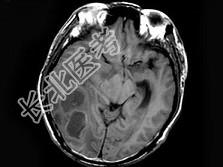

- 单项选择题男,47岁, 发热、头痛、呕吐1周,MRI检查, 最可能的诊断是 ( )

A、脑转移瘤

B、脑脓肿

C、胶质瘤

D、血吸虫性脑病

E、未见异常